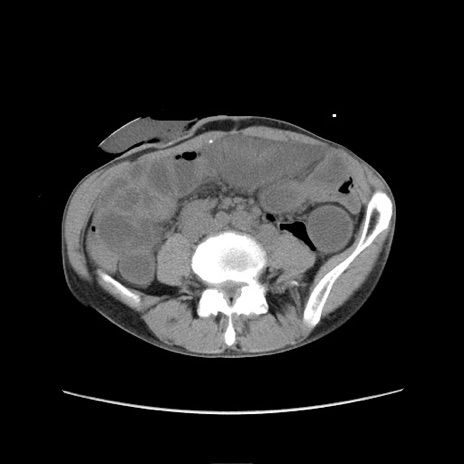

症例11(横断像)

【症例】 60歳代男性

【主訴】 下腹部痛

【現病歴】 本日夜中より下腹部痛の症状認め、受診。

【既往歴】 膀胱癌(膀胱全摘+尿管皮膚瘻術) 、胃癌術後

【身体所見】 BT 35.3℃、PR 58/min、BP 136/98mHg、腹部平坦、軟、腸蠕動音±、ストマ留置あり、左上腹部~正中部に圧痛あり、反跳痛なし。

【データ】WBC 5100、CRP0.01